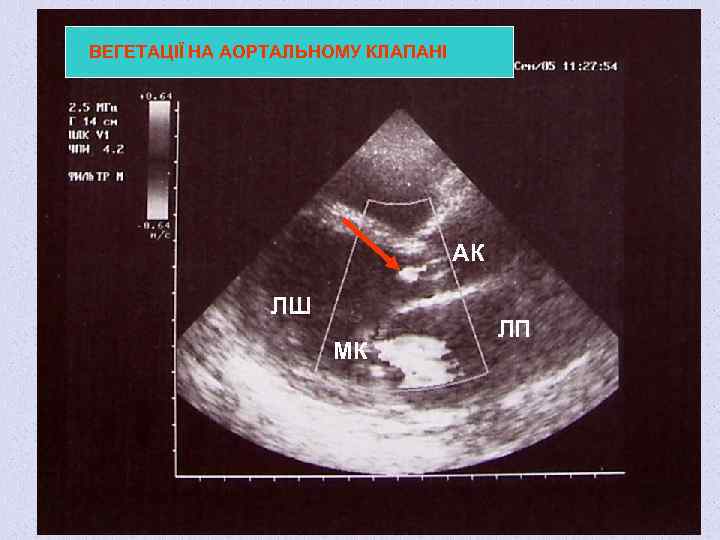

ВЕГЕТАЦІЇ НА АОРТАЛЬНОМУ КЛАПАНІ АК ЛШ МК ЛП